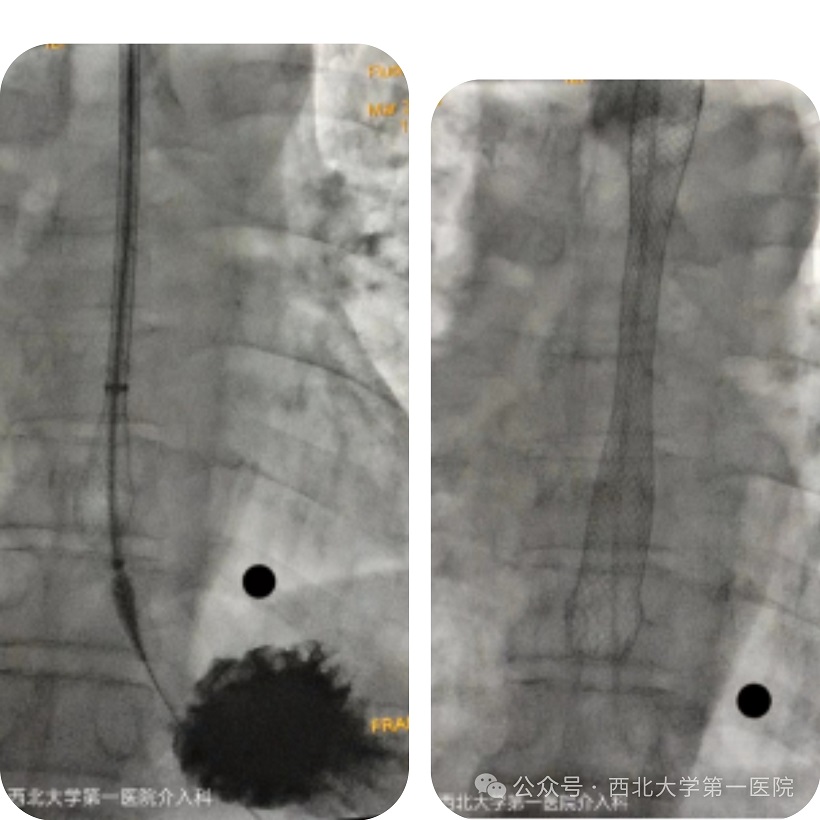

排除手术禁忌症后,介入科专家团队在孙教授的指导下,为患者实施内镜下行食管支架置入术。手术顺利,术后进行了食道造影,显示造影剂顺利通过狭窄处到胃内。

术后第二天,患者给予流质饮食,未见明显梗阻及呕吐现象,患者食管梗阻解除,为后期进一步治疗提供了可能。